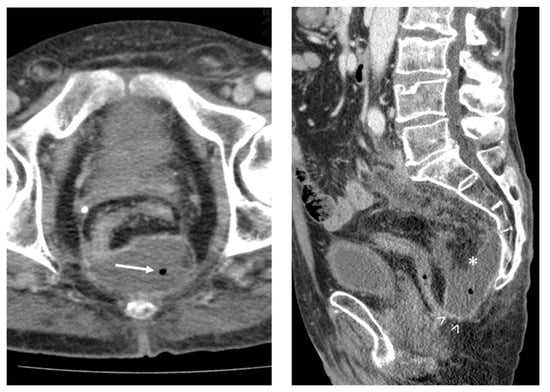

Figure 1. An 83-year-old woman with chambered pleural effusion (→) and CT attenuation of 8 HU. After percutaneous drainage, no pathogen was detected by microbiological approach.

Figure 2. A 63-year-old man with presacral abscess (*), demonstrating gas entrapment (→), wall enhancement (>), fat stranding and CT attenuation of 29 HU. Microbiology after percutaneous drainage confirmed infection.